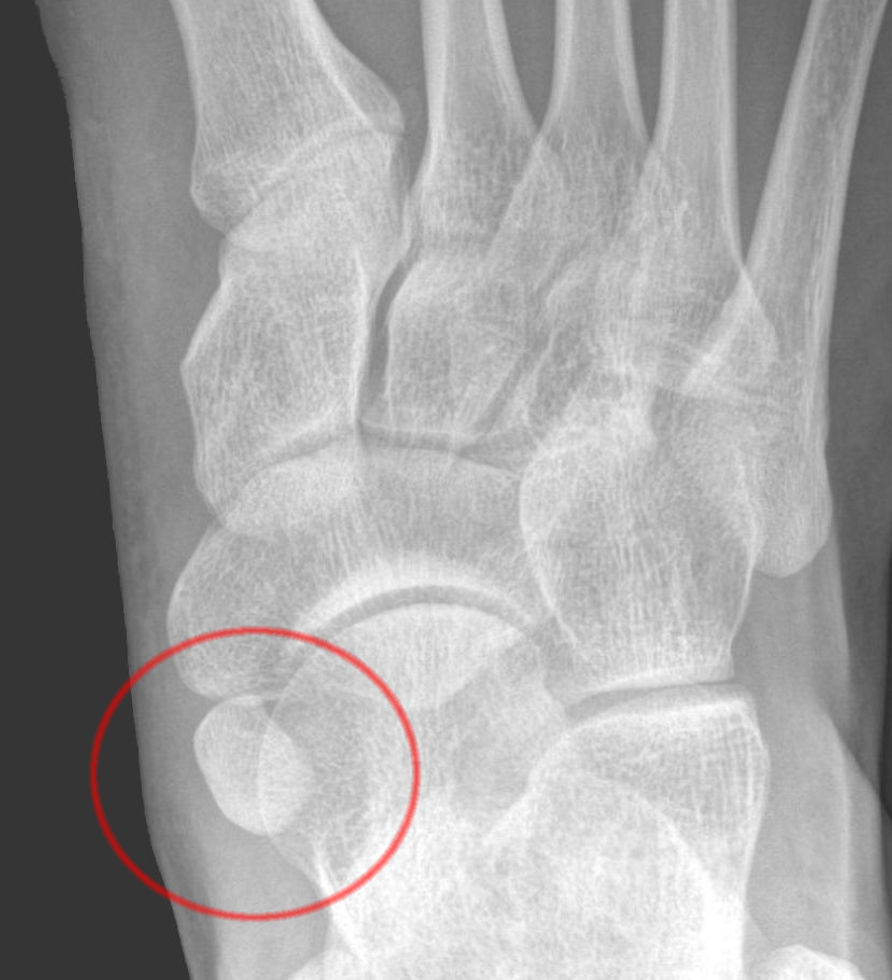

from ultraraastaja.webnode.fi

Os tibiale externum rasitusosteopatia Ultraraastaja

Os tibiale externum rasitusosteopatia Ultraraastaja Rasitusosteopatia Hoito Mitä jos toipilasajan käyttäisikin hyväksi? rasitusmurtumaa edeltävät luumuutokset eli rasitusosteopatia voidaan sitä vastoin todeta jo oireiden alkaessa. tuore rasitusmurtuma voi parantua, jos rajoitetaan nikamakaarta kuormittavaa liikuntaa. hoidon kulmakivinä ovat oireiden aikainen tunnistaminen ja varhainen diagnoosi, riittävä harjoitustauko ja tarvittaessa. Pääasiallinen hoito rasitusmurtumassa on kuormituksen ja lisärasituksen. Rasitusosteopatia Hoito.

Os tibiale externum rasitusosteopatia Ultraraastaja Rasitusosteopatia Hoito Pääasiallinen hoito rasitusmurtumassa on kuormituksen ja lisärasituksen. Mitä jos toipilasajan käyttäisikin hyväksi? tuore rasitusmurtuma voi parantua, jos rajoitetaan nikamakaarta kuormittavaa liikuntaa. rasitusmurtumaa edeltävät luumuutokset eli rasitusosteopatia voidaan sitä vastoin todeta jo oireiden alkaessa. hoidon kulmakivinä ovat oireiden aikainen tunnistaminen ja varhainen diagnoosi, riittävä harjoitustauko ja tarvittaessa. Rasitusosteopatia Hoito.